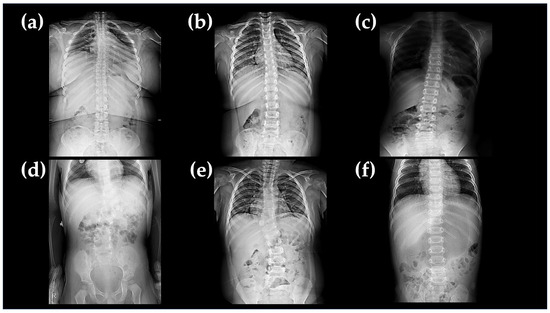

2.1.4. Family D

| A-III-1 | F/12 | present | present | mild | no | present | scoliosis |

| A-III-4 | M/6 | present | no | moderate | no | present | scoliosis |

| B-II-2 | M/5 | present | present | moderate | present | no | scoliosis |

| D-II-1 | M/3 | present | no | moderate | no | present | vertebral dysplasia no |

| E-II-1 | M/1 | present | present | mild | no | no | vertebral dysplasia no |